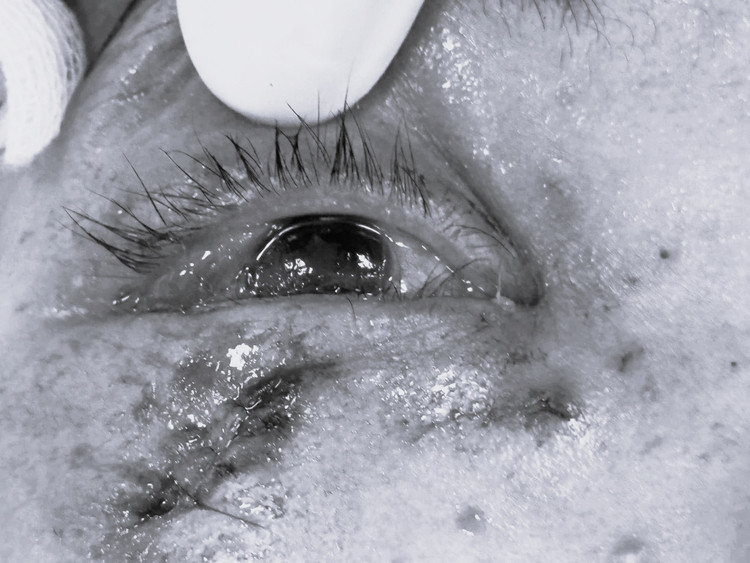

Ngay sau khi xảy ra tai nạn, bệnh nhân được chuyển đến cấp cứu tại Bệnh viện Mắt Hải Phòng. Tại đây, kíp trực nhanh chóng hội chẩn và xác định bệnh nhân bị chấn thương đụng dập, vỡ nhãn cầu mắt phải, xuất huyết tiền phòng và có vết thương ở da mi dưới.

| Mắt bệnh nhân bị tổn thương. Ảnh BVCC |